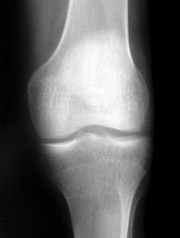

Razlozi za prekomerno trošenje hrskavice su višestruki, pa se među najvažnije uzroke nastanka osteoartritisa, pored urođenih deformacija zglobova, ubrajaju prekomerna telesna težina, konstantno opterećenje zbog prirode posla te mikro ozlede hrskavice nastalih tokom rekreativnih sportskih aktivnosti ili nepravilno doziranih treninga. Najčešće se artritične promene javljaju na zglobovima kolena, kuka, ručnim zglobovima i ramenom pojasu.